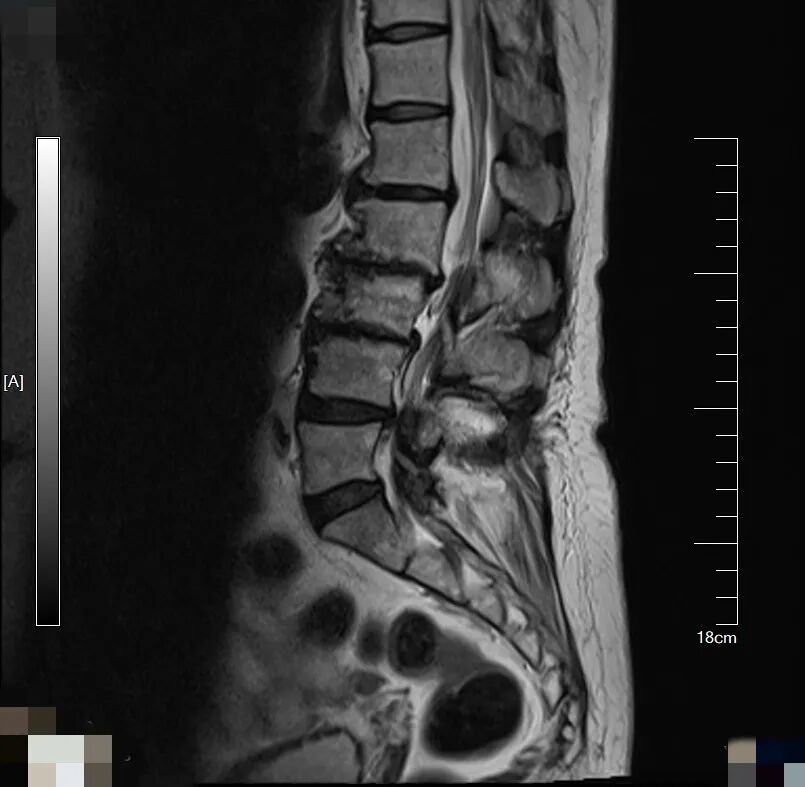

▲影像学检查提示退变性脊柱侧弯、

椎间盘突出、腰椎滑脱、腰椎管狭窄